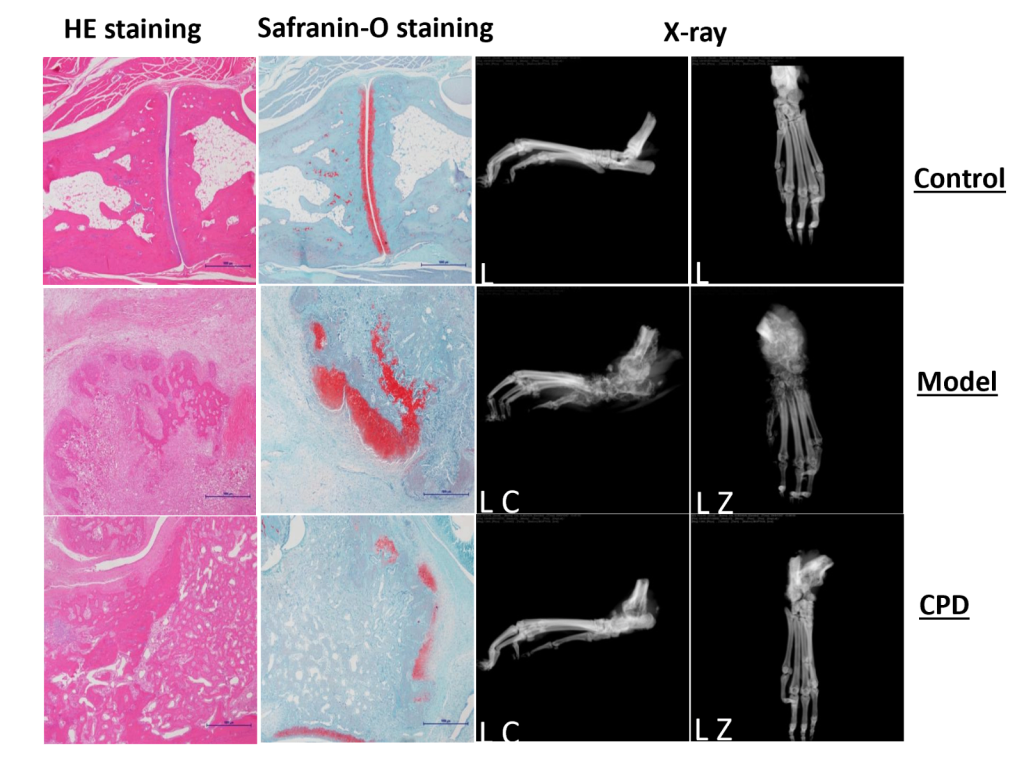

Model anatomy and histopathological analysis confirm model adequacy for preclinical RA compound testing.

Also, both clinical score and joint swelling show model relevancy for RA and responsiveness to tofacitinib, a Janus kinase (JAK) inhibitor.